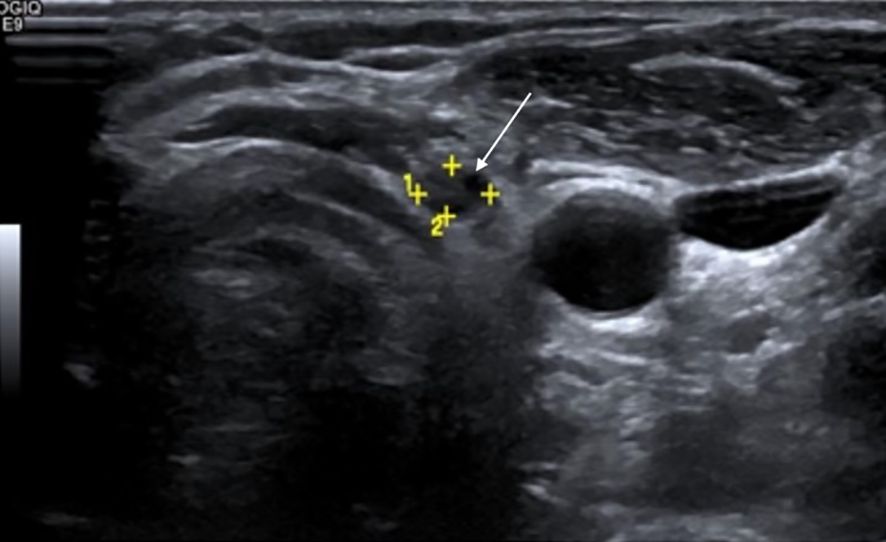

Background: Differentiated thyroid cancer (DTC; including papillary and follicular thyroid cancers) has favourable survival outcomes, with related mortality below 10%. However, 20–30% of patients experience recurrence. Surveillance primarily relies on neck ultrasonography (US) and serum thyroglobulin (Tg) assessment. Purpose: This study evaluated the diagnostic performance of neck US in detecting locoregional recurrence following total thyroidectomy and compared its effectiveness with serum Tg. Materials and Methods: This retrospective, single-centre study analysed 941 DTC patients who underwent total thyroidectomy and neck US between 2009 and 2019. Suspicious US findings were correlated with serum Tg levels and anti-thyroglobulin antibody status. Disease persistence (<6 months) /recurrence (>6 months) was confirmed via fine-needle aspiration cytology/biopsy, iodine scintigraphy, CT, or PET-CT. Patients without US-detected lesions were assessed clinically, biochemically, and via follow-up US. Results: Neck US had a sensitivity of 98.9%, specificity of 63.1%, positive predictive value (PPV) of 50.7%, negative predictive value (NPV) of 99.3%, and an accuracy of 73.01%. Serum Tg (cutoff 1.8 ng/ml derived from receiver operating characteristic analysis) had a sensitivity of 69.2%, specificity of 91.8%, PPV of 61.4%, NPV of 94.1%, and an accuracy of 88.28%. Among 149 patients with US-detected lesions and Tg <1.8 ng/ml, 22 (14.8%) had locoregional recurrence. Five of 43 patients with Tg <0.1 ng/ml had confirmed recurrence. Among lymph nodes ≤6 mm in short-axis diameter with an indistinct fatty hilum, 69.6% were benign. Persistence was detected in 38.5% of patients within six months post-treatment, whereas most true recurrences (61.5%) manifested after six months. Conclusion: Neck US is highly sensitive but moderately specific for detecting locoregional recurrence post-thyroidectomy, complementing Tg. Study limitations include its retrospective design, single-centre setting, and lack of inter-observer variability assessment. A risk-adapted multimodal surveillance strategy with 6-monthly US for two years is recommended.